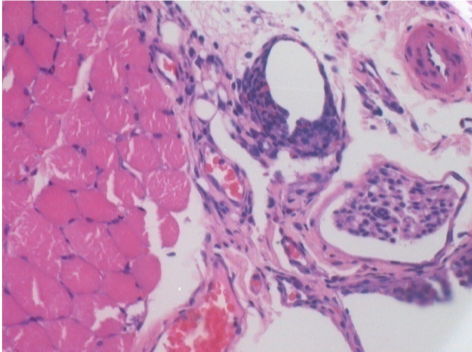

10 days after Endopeel Injection 0.1ml in the right pretibial muscle.

Here you may see the formation of the vacuoles which are surrounded by lymphocytes. Vacuoles are different from tissue necrosis . The presence of lymphocytes is related to the permeability of the cell membranes.